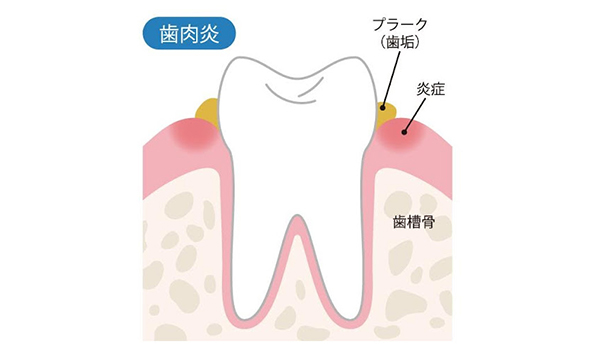

歯肉炎とは

歯肉炎とは、細菌によるダメージが骨ではなく歯ぐきだけに留まっている状態を指します。

プラーク1mgのなかには、およそ300種類1億個の細菌が存在しており、歯ぐきに付着することで炎症を引き起こします。これが歯肉炎の始まりです。

つまり、お口の中に細菌が多い状態が続くと歯肉炎、歯周病の原因になります。